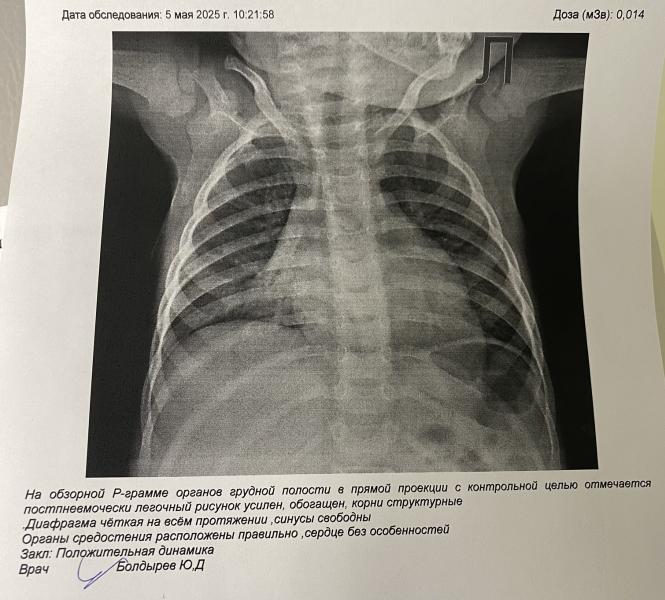

Добрый день. 23.04 обнаружили правостороннюю нежнедолевую пневмонию. Прошли курс уколов. Сегодня контрольный рентген был. Получается полностью пневмония не ушла и нужны еще антибиотики? И за сколько она вообще проходит. К педиатру после обеда, но мне сейчас не терпится узнать

Неинформативно делать рентген через 10 дней. Мы так один раз попали к педиатру. Пневмония, пропили антибиотик, симптомы все ушли через пару дней. Через 10 дней контрольный рентген, по которому изменения еще есть, и нам новый антибиотик. Пошли в докдети, где нам объяснили, что рентген раньше, чем через месяц не делают, послушали и отпустили как здоровых))